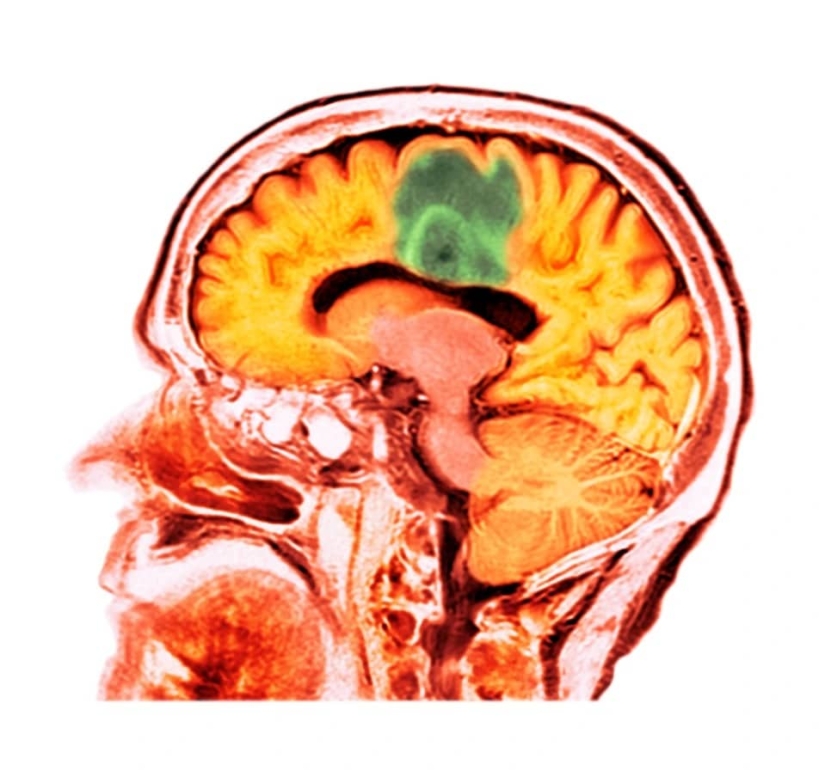

El cáncer de cerebro es una de las formas más graves de esta enfermedad, que es difícil de tratar. Pero un grupo de científicos de Toronto encontró una salida usando rayos de ultrasonido. Con su ayuda, puede pasar de forma segura a través de la barrera hematoencefálica y garantizar el flujo de medicamentos.

Este año, cuatro mujeres con cáncer de mama, cuyas metástasis llegaron al cerebro, participaron en los ensayos. Fueron tratados con ecografía focalizada por resonancia magnética. Gracias a sus ondas, herceptin, un fármaco basado en anticuerpos, se administró al tejido cerebral. Fue absorbido con éxito por el cuerpo y contribuyó a la reducción de tumores sin dañar los tejidos sanos.